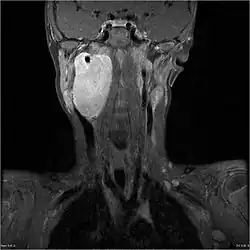

| MRI of a ganglioneuroblastoma found in the head and neck of a 7 year old Caucasian male. | |